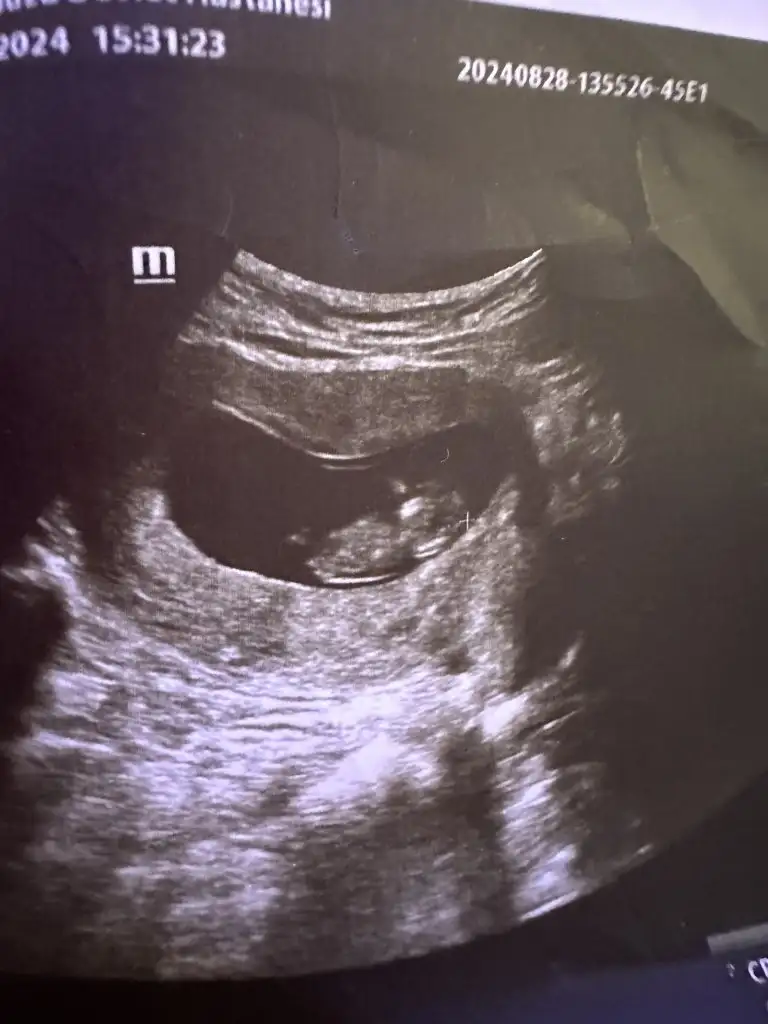

Kızlar bizde haberler birazcık can sıkıcı ama inanıyorum ki Allahın izniyle bebeğime de bana da birşey olmadan atlatacağız. Benim çok enfeksiyon sorunum oluyordu. Bunun için tedavi görüyordum yine. Bu enfeksiyonlardan kaynaklı olabileceği muhtemel şekilde dünkü perinotoji muayenesinde gördük ki benim serviks boyu normalden kısaymış. Şimdi onu takibe aldık. Progestan hap ve antibiyotik verdi hepsi ağızdan. Bu kısalık kısalmaya devam ederse Ptesi günü ameliyatla dikiş atacak. Biz de tatil planları yapıyorduk güzel güzel ama hepsi yalan oldu çünkü burdan uzaklaşmayın dedi doktor.

Muayenede gördük ki bebiş maşallah çok iyi el ense yapmış yatıyordu. Çok şükür onun bir sıkıntısı yok. Benim bu servikal sıkıntıyı da çözersek bir şey olmayacak biliyorum. Ameliyat deyince biraz korktular bizimkiler ama ben bir sorun olacağını düşünmüyorum. Bu tarz sorun yaşayan vardı galiba ne durumdasınız full yatar şekilde geçmiyor değil mi sonraki süreç yine normal hayatımıza dönebiliriz diye biliyorum yani kendimizi çok yormayacak şekilde. Çünkü Allahtan çalışmıyorsun dedi bana doktor. Varsa yaşayan dertleşelim.